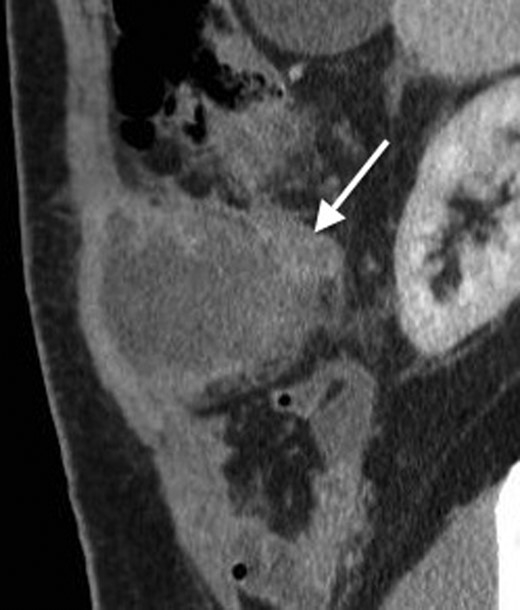

A coronal CT with contrast showing the tail of the appendix communicating with the appendiceal abscess.

His past surgical history included conservatively managed renal calculi and left inguinoscrotal herniorrhaphy. Right hypochondrial palpation identifying a tender, well-defined, hard, smooth edged, non-pulsatile, non-fluctuant mass (10 × 9 cm). Observations were within normal limits and systemic examinations unremarkable. Haematological results showed the following: albumin 27, WCC 15.7, neutrophils 11.0, CRP 341, amylase 20. Urinalysis, chest and abdominal radiographs (AXR) were normal. Initial resuscitative management was commenced and a contrast enhanced computed tomography (CT) performed. This demonstrated an anterior abdominal wall collection (7 cm) arising from an RUQ appendiceal abscess secondary to acute appendicitis (Figs 1 and 2). Consequent ultrasound (US) guided drainage and pigtail catheter insertion removed 50 ml of frank pus, which isolated pathogens sensitive to penicillin and erythromycin. Following 3 days of intravenous piperacillin and tazobactam (Tazocin®) he was discharged with oral erythromycin. An out-patient barium follow-through and colonoscopy were unremarkable.